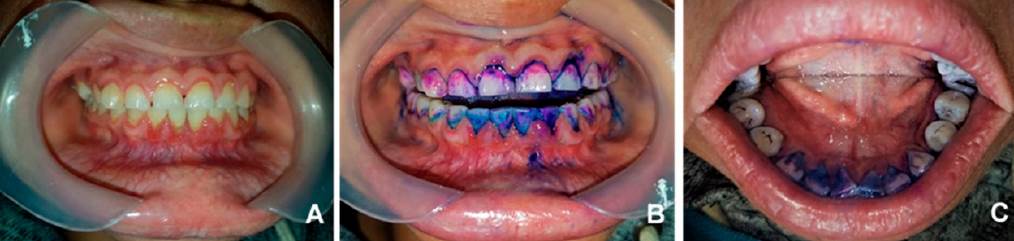

La intensidad del dolor se evaluó mediante la escala visual analógica (EVA)11-12, en donde el dolor se clasifica como leve de 1 a 3 puntos, moderado de 4 a 6 puntos y severo de 7 a 10 puntos. La inflamación gingival se midió con el índice gingival de Löe y Silness13,14, que permite clasificar la inflamación en grado 0= ausencia de la misma; grado 1= inflamación leve; grado 2= inflamación moderada y grado 3= inflamación severa. La periodontitis fue evaluada según la clasificación de enfermedades y condiciones periodontales y periimplantarias del taller mundial de 201715, diagnosticándose en periodontitis Estadio 2 y Grado B, con pérdida de inserción clínica (CAL) interdental de 4 mm y profundidad máxima de sondeo de 5 mm. El índice de sangrado "papilar"14,16 se determinó en las zonas mesial y distal de cada diente y se clasificó de la siguiente manera: 0= sin sangrado; 1= un punto de sangrado discreto; 2= varios puntos de sangrado aislados o una sola línea de sangrado; 3= el triángulo interdental se llena de sangre después del sondeo y 4= sangrado profuso inmediatamente después del sondeo con sangre fluyendo hacia el diente y el margen de la encía. La clasificación de movilidad dental de Miller17,18 se evaluó e interpretó de la siguiente manera: grado 0= sin movimiento; 1= aumento distinguible en la movilidad; 2= movilidad visible <1 mm; y 3= movilidad >1 mm en cualquier dirección. Finalmente, la placa dental bacteriana se determinó por el índice O’Leary19,20 con un gel revelador de placa dental de tres tonos (GC Tri Plaque ID GelTM, GC International AG, Lucerna, Suiza) capaz de teñir la placa dental en tres colores diferentes (Figura 1). Se realizó una evaluación del tipo de placa considerando su patogenicidad y se clasificó de la siguiente manera: placa de alto riesgo (color azul claro, con pH <4.5), placa antigua (color azul, >48 h) y placa nueva (color rosa). La evaluación previa y posterior al tratamiento del dolor e inflamación gingival, el sangrado al sondeo, la movilidad dental, la pérdida de inserción clínica y el índice de placa dental se realizaron en todos los dientes y tejidos gingivales del cuadrante maxilar derecho (cuadrante 1) y del cuadrante mandibular derecho (cuadrante 4), de acuerdo con la nomenclatura de la Federación Dental Internacional (FDI). La investigación fue aprobada por la Comisión Institucional de Ética del Hospital General Dr. Miguel Silva con número de registro 460/01/09; cumplió con lo establecido en la Ley General de Salud de México, y se realizó de acuerdo con los principios éticos para las investigaciones médicas en seres humanos de la Declaración de Helsinki de la Asociación Médica Mundial (AMM). La paciente firmó el consentimiento informado para participar en el estudio.

Figura 1 A) Se observa una inflamación de grado 2, según el índice de Löe y Silness, en todo el margen gingival de los dientes maxilares y, en los dientes mandibulares se muestra una inflamación de grado 3 del tejido gingival, de los dientes 33 al 44. El resto del tejido gingival de los dientes mandibulares muestra una inflamación de grado 2 (dientes: 37, 36, 35, 34, 45, 46 y 47). B) Hay abundante placa de alto riesgo (azul claro, con pH<4,5), placa antigua (azul, >48 h) y placa nueva (rosa) en dientes, surcos y márgenes gingivales. C) Presencia de placa dental en la cara lingual de los dientes mandibulares, principalmente en los incisivos.